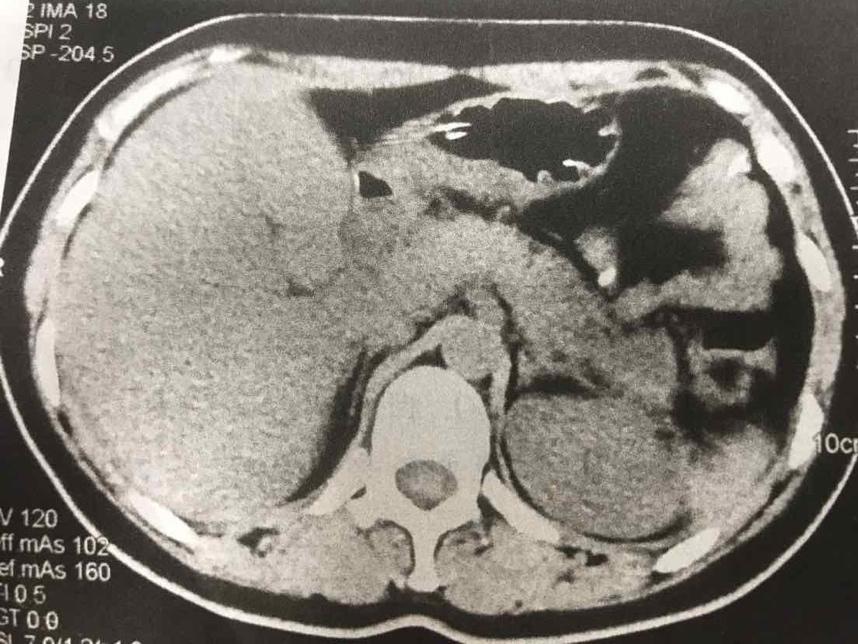

摘要:本文介紹了急性胰腺炎的最新分型,包括其分類標(biāo)準(zhǔn)和特點(diǎn)。文章還提到了一天的奇妙之處與急性胰腺炎分型之間的聯(lián)系,強(qiáng)調(diào)了及時(shí)診斷和治療的重要性。全文旨在提高人們對急性胰腺炎的認(rèn)識,以便更好地預(yù)防和治療該疾病。